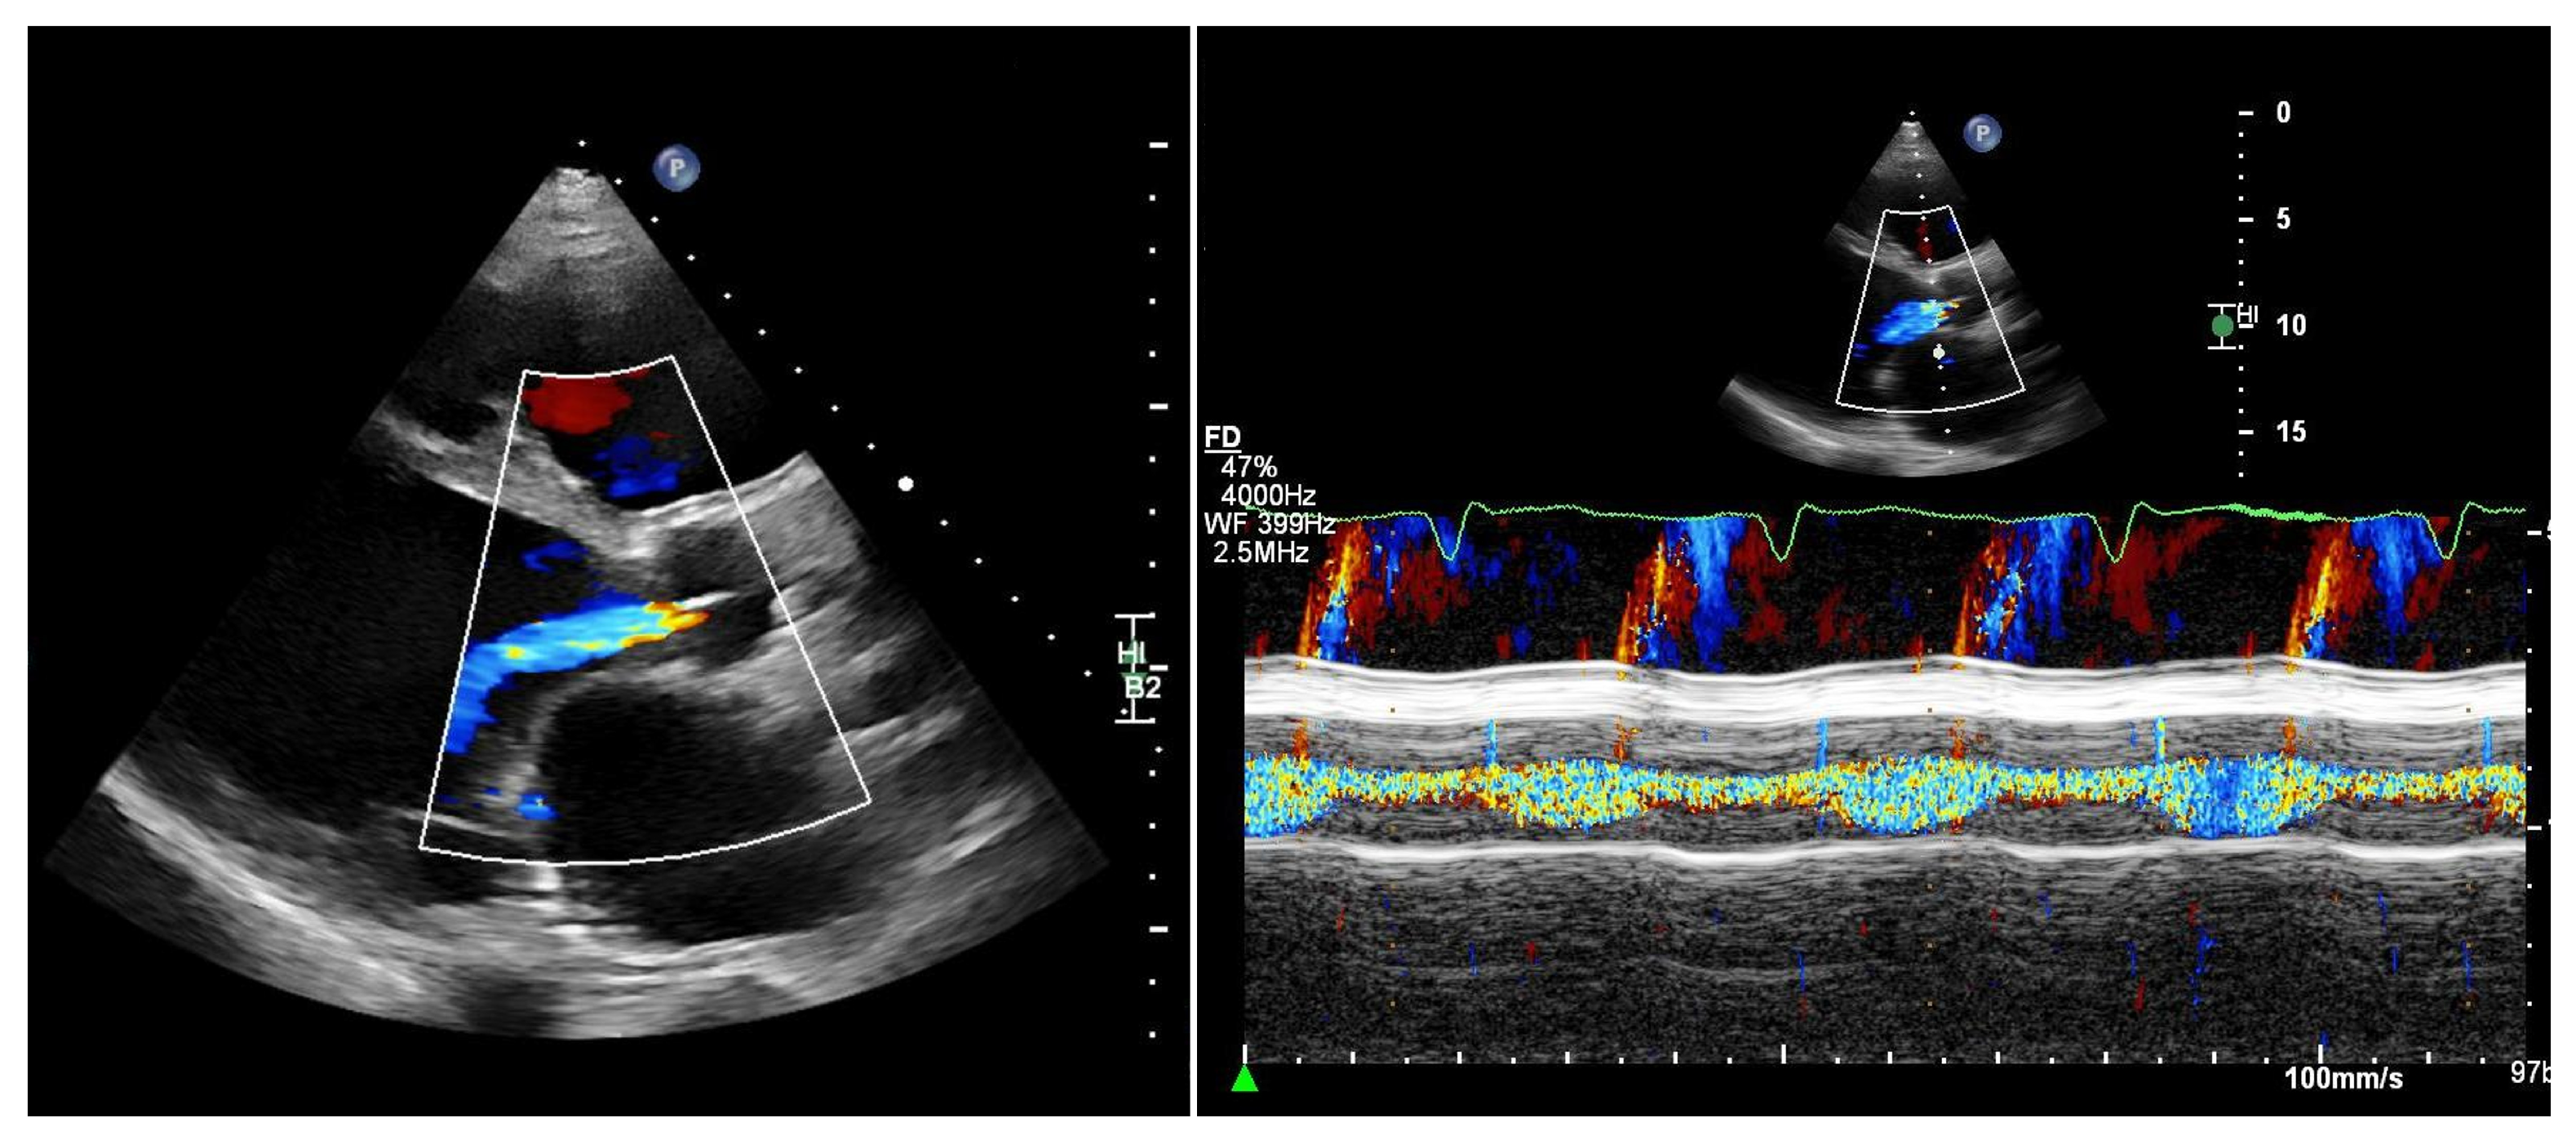

More recently, a novel transthoracic pulse-wave Doppler-based parameter obtained from a modified right-sided parasternal window has been proposed. By interrogating the LVAD outflow graft, diastolic flow acceleration and the systolic-to-diastolic peak velocity ratio (S/D ratio) can be calculated [28]:

- Outflow graft S/D ratio < 5.0 indicates at least moderate AR;

- Diastolic acceleration > 49 cm/s suggests significant AR.